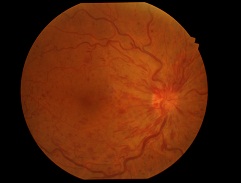

先日ハードレンズを処方した方の写真です。

先日ハードレンズを処方した方の写真です。